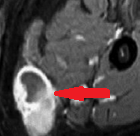

Αξονική τομογραφία κοιλίας. Φεβρουάριος 2017. Εμφανίζεται η υποτροπή του οπισθοπεριτοναϊκού αγγειοσαρκώματος (κόκκινα βέλη)